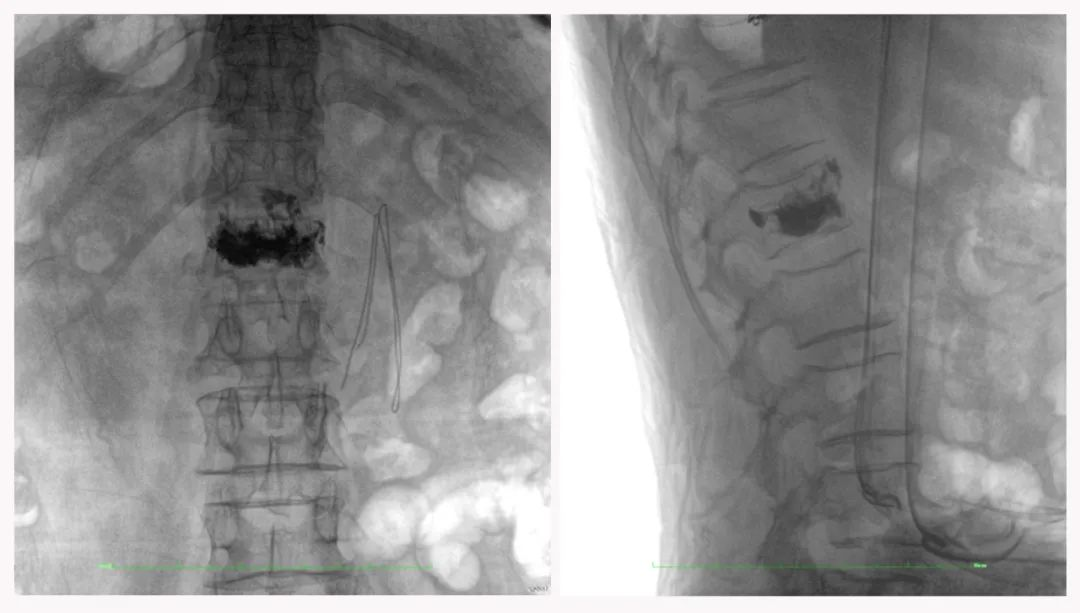

病例3:超聲支氣管鏡下肺活檢(80歲)

三維C形臂還可以創新性地應用在呼吸介入領域。例如,在經皮穿刺或經支氣管鏡肺結節活檢、定位、消融等場景中,用于確認工具是否到達病灶、消融范圍是否完全覆蓋病灶等。

二維影像無法準確判斷工具是否到達病灶

三維各切面影像都顯示工具達到病灶內